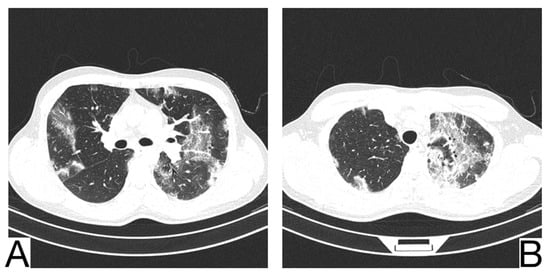

Imaging characteristics for differential diagnosis are (Figure 10A,B): the absence of the cobblestone in simple pulmonary eosinophilia (SPE), also known as Loeffler syndrome); pleural effusions, centrilobular nodules, and thickening of lar bundles in acute eosinophilic pneumonia []; centrolobular consolidations with occasional frosted glass and cobblestone opacities in chronic eosinophilic pneumonia; additional findings in chronic eosinophilic pneumonia are represented by nodules, atelectasis, band opacities, and pleural effusions [,].

Figure 10. Chronic eosinophilic pneumonia (A,B). Consolidation throughout both lungs. Note. Case courtesy of Dr. Henry Knipe, Radiopaedia.org, rID: 39331.